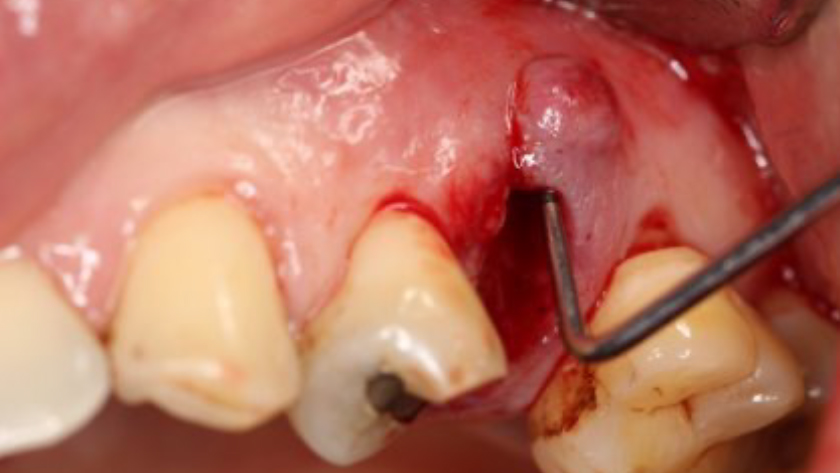

Tooth 13* required extraction in a 54-year-old male patient. The buccal bone was absent. Goal was to restore the site with an implant.